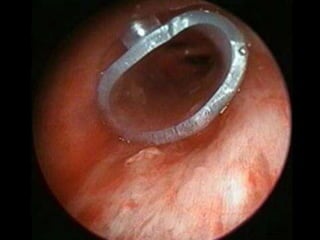

Fistula Bronquial

- Aseptizada la cámara pleural se podrán realizar:

- Tratamiento endoscópicas (Cauterización repetidas, sellantes

de fibrina) habitualmente en fístulas <3mm de diámetro.